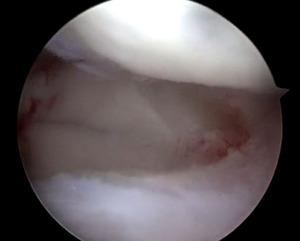

A MRI of the knee revealed a displaced tear of the anterior and posterior horns of the lateral meniscus (Figures 2 & 3).